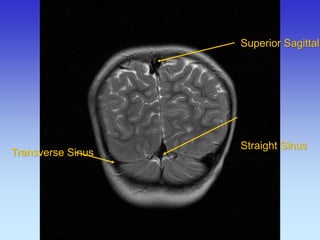

Superior Sagittal Sinus

Straight Sinus

Transverse Sinus

Superior Sagittal Straight Sinus

Cerebellum

Occipital Lobe